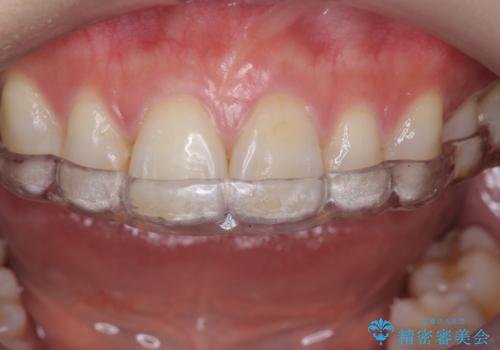

歯ぎしりや歯の保護のためにナイトガードを作製しました。

ナイトガードは歯の保護だけではなく、矯正治療後の歯の後戻りの防止もしてくれます。